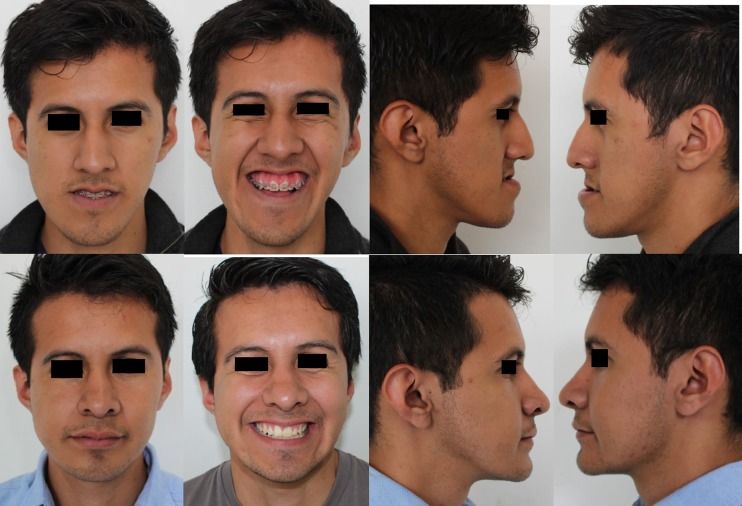

It moves cheekbones upward, give so much under eye support and even change orbital shape. Also widen face and change gonial angle. Is it modified lefort 3?